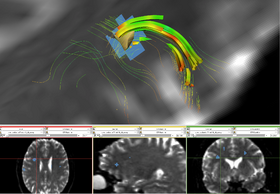

[[Image:TractsLesionZoomOverlay.png‎|thumb|280px|Image Acquisition]]

• DTI Analyses

filling this in still

Image Acquisition